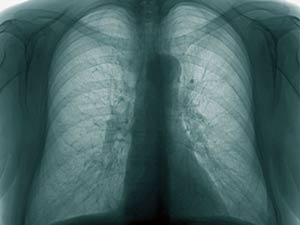

മൂത്രപരിശോധനയിലൂടെ ക്ഷയം കണ്ടെത്താം

ഇതിനേക്കാള് എത്രയോ ചെലവുകുറഞ്ഞതും വേഗതയേറിയതുമായ രീതിയായിരിക്കും മൂത്രപരിശോധന. ഇതു സംബന്ധിച്ച റിപ്പോര്ട്ട് അമേരിക്കന് കെമിക്കല് സൊസൈറ്റി ജേര്ണലില് പ്രസിദ്ധീകരിച്ചു കഴിഞ്ഞു.

വൊളട്ടയില് ഓര്ഗാനിക് കോംപൗണ്ടുകള് ക്ഷയരോഗികളിലും ആരോഗ്യമുള്ള ഒരാളിലും വ്യത്യാസപ്പെട്ടിരിക്കും. ഈ കോംപൗണ്ടുകളുടെ സാന്നിധ്യം തിരിച്ചറിയാന് ഒരു ഇലക്ട്രോണിക് ഉപകരണം വികസിപ്പിച്ചെടുത്താല് മാത്രം. സെക്കന്റുകള്ക്കുള്ളില് ഒരാള്ക്ക് രോഗമുണ്ടോ ഇല്ലയോ എന്നു വ്യക്തമാവും-പരീക്ഷണങ്ങള്ക്ക് നേതൃത്വം നല്കുന്ന വീരേന്ദര് സിങ് ചൗഹാനും രഞ്ജന് കുമാര് നന്ദയും അറിയിച്ചു.